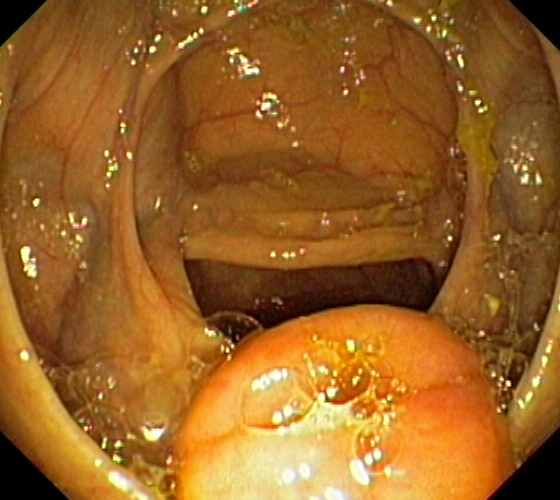

Ileocaecal valve